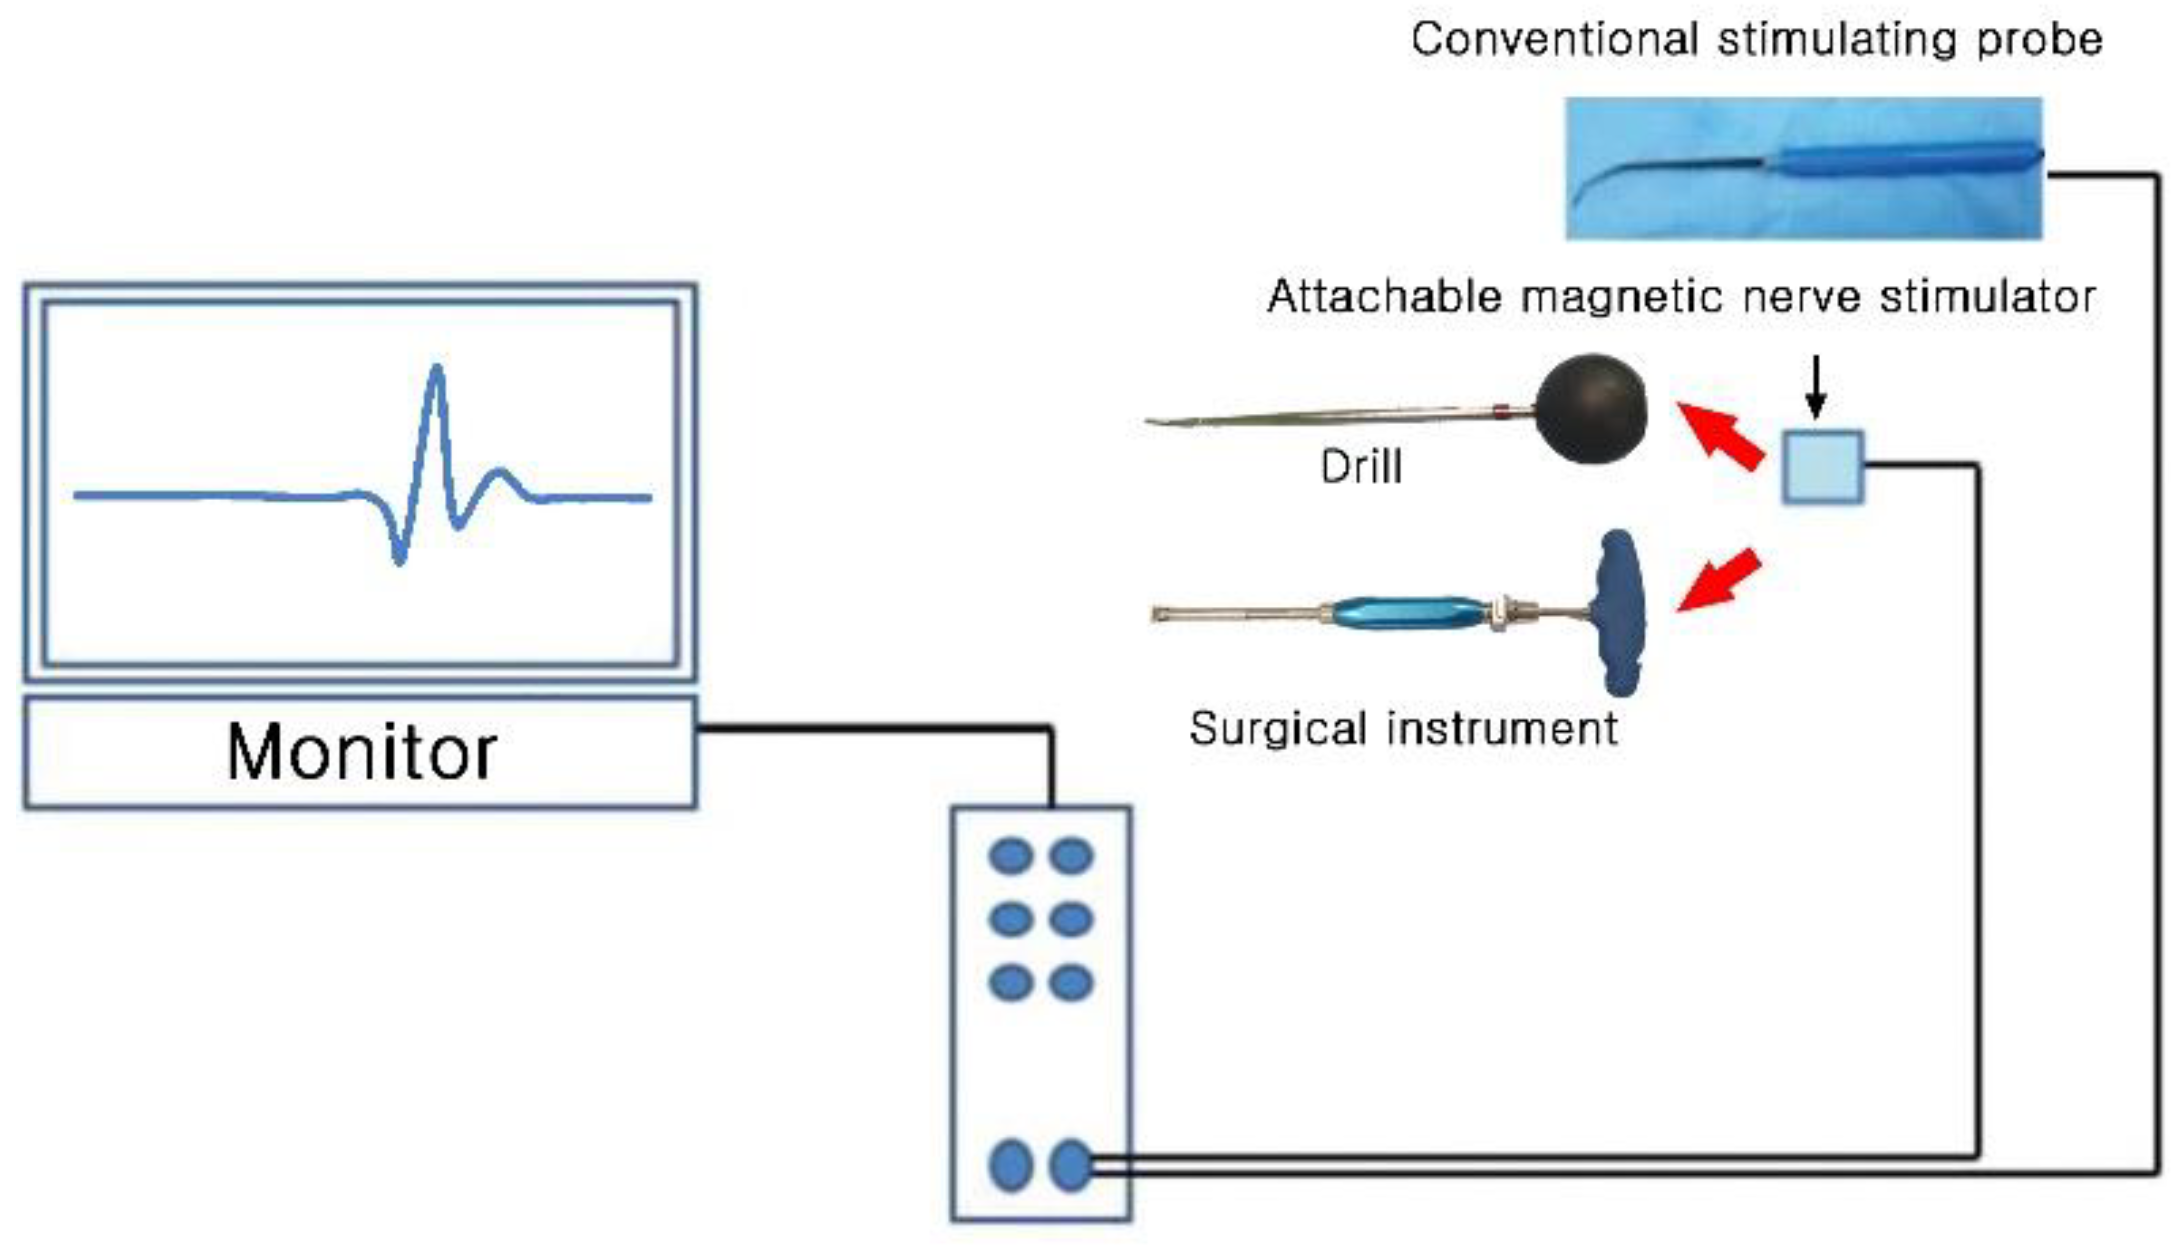

2. Materials and Methods

2.1. Animal Experiment